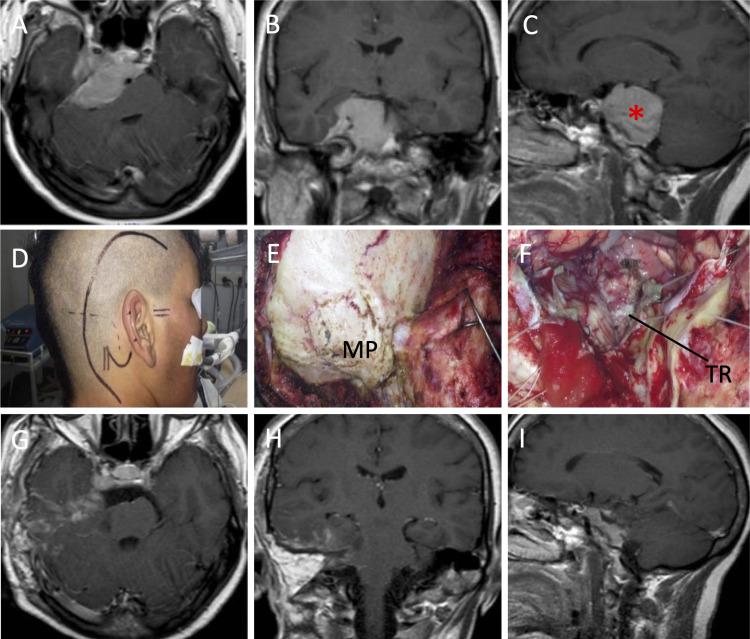

Combined Presigmoid-Subtemporal Approach in a Semi-Sitting Position for Petroclival Meningiomas: A Technical Report.

The removal of petroclival meningiomas (PMs) is considered a neurosurgical challenge due to the critical mobilization of key neurovascular structures. Limited knowledge about the benefits of operating on patients with PMs using the combined presigmoid-subtemporal approach (CPSA) in a semi-sitting position has precluded its generalizability. We report on ten patients with PMs operated in a semi-sitting position using CPSA. We remark that before the surgical approach was accomplished in our group of patients, the CPSA via semi-sitting position was conducted and standardized in six adult cadaveric heads. The neuroanatomic dissections made in cadavers allowed us to confidently use CPSA in our set of patients. There were no comorbidities, perioperative complications, or deaths associated with the surgical procedure. CPSA via a semi-sitting position can be considered a safe approach to remove PMs.

由于关键神经血管结构的关键游离,岩斜区脑膜瘤(PMs)的切除被认为是一项神经外科挑战。关于采用联合乙状窦前-颞下入路(CPSA)在半坐位对PMs患者进行手术的益处,了解有限,这妨碍了该方法的推广。我们报告了10例采用CPSA在半坐位接受手术的PMs患者。我们注意到,在我们的患者组完成手术入路之前,通过半坐位的CPSA在6个成人尸头上进行并标准化。在尸体上进行的神经解剖使我们能够在我们的患者组中自信地使用CPSA。没有与手术相关的合并症、围手术期并发症或死亡。通过半坐位的CPSA可被认为是切除PMs的一种安全方法。